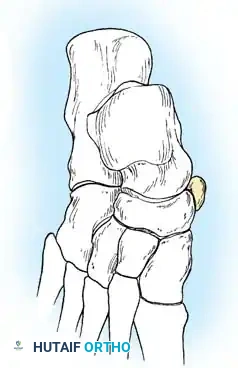

العظمة الزورقية الإضافية

في بعض الحالات، يولد الشخص بعظمة إضافية بارزة تسمى العظمة الزورقية الإضافية (Accessory Navicular). ترتبط هذه العظمة بوتر العضلة القصبية الخلفية، وقد تسبب ألماً وتسطحاً في القدم، مما يتطلب استئصالها جراحياً وإعادة توجيه الوتر لاستعادة قوس القدم.

جراحة استئصال العظمة الزورقية الإضافية

تُعرف هذه العملية بإجراء "كيدنر" (Kidner Procedure). يتم إجراؤها للمرضى الذين يعانون من ألم مزمن بسبب بروز العظمة الزورقية الإضافية.

تتضمن الجراحة عمل شق جراحي صغير، وفصل العظمة الإضافية عن وتر العضلة القصبية الخلفية، ثم استئصال العظمة الزائدة وتسوية سطح العظم الأصلي. بعد ذلك، يتم إعادة خياطة الوتر وتثبيته بقوة لدعم القوس الداخلي للقدم.